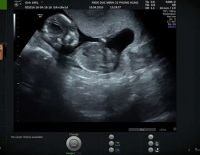

Thai 14 tuần biết trai hay gái chưa? DẤU HIỆU NHẬN BIẾT là gì?

Trước khi trả lời câu hỏi “Thai 14 tuần biết trai hay gái chưa?”, hãy cùng Phòng khám Bác sĩ Điệp tìm hiểu về sự phát triển của thai nhi tuần thứ 14 nhé! Thai nhi 14 tuần (Tam cá nguyệt thứ 2) – Phát...